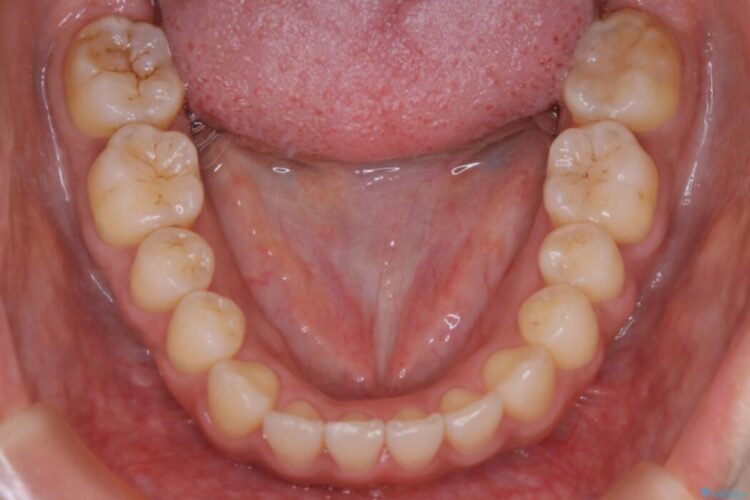

治療後について

きちんと装着時間を守っていただいたこともあり、きれいな歯並びを獲得できました。

マウスピースとマイクロインプラントの併用により矯正するための隙間を確保し、治療期間は長くなりますが非抜歯できれいな歯列弓を得ることができます。